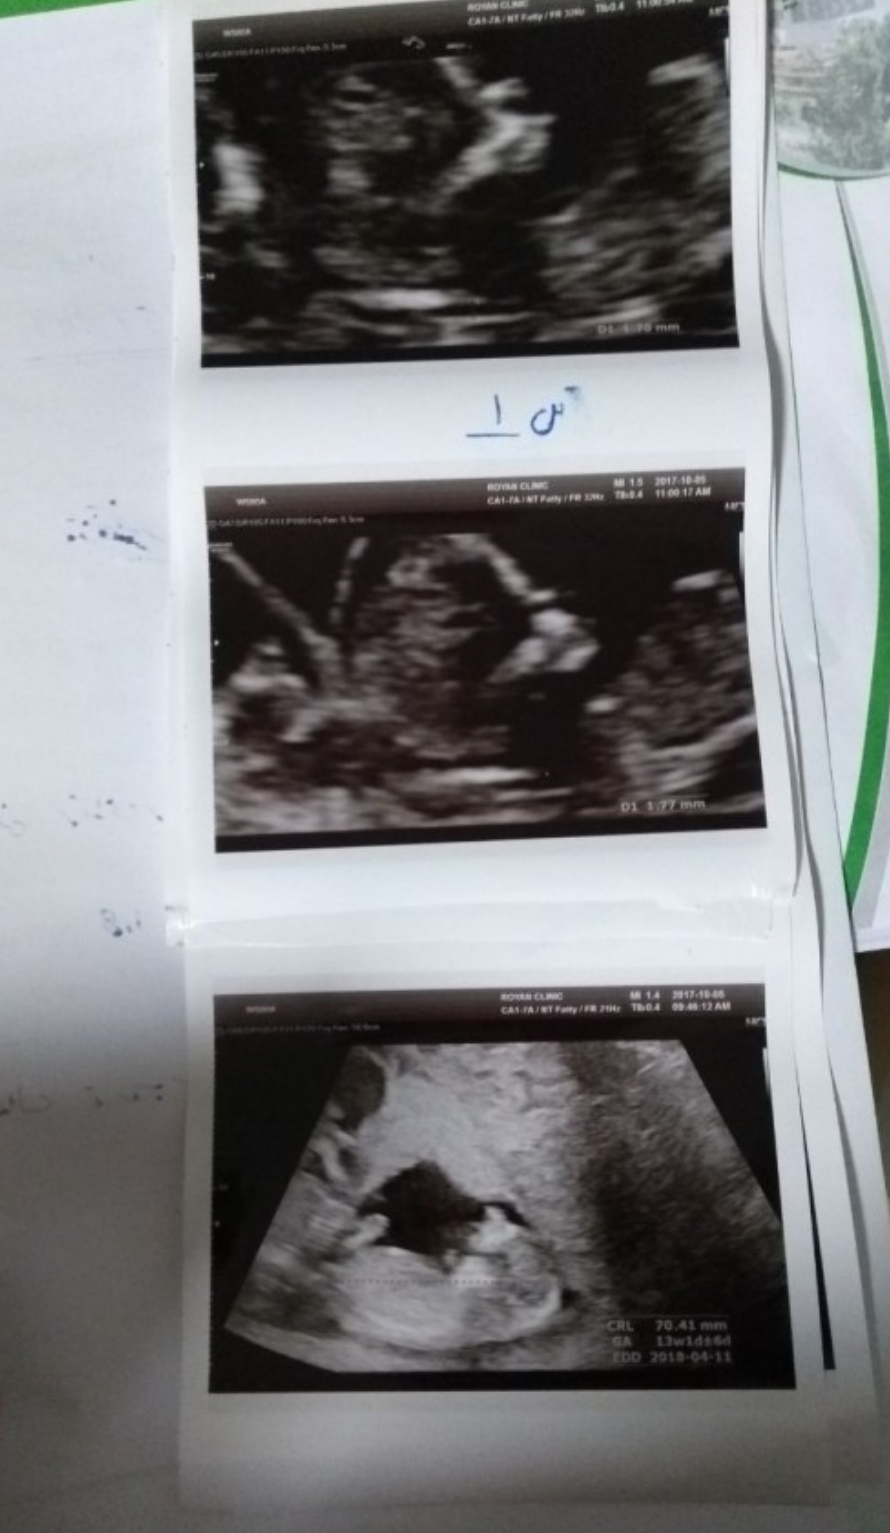

۹۹/۹/۹ قرار بود بی بی چکم مثبت بشه اما خدای رحمان الرحیمم زودتر عافلگیرمون کرد یعنی۹۹/۸/۱۹😍خدایااااا شکرت.ان شاءالله همه منتظرا این طعم را بچشن🥰وقتی رفتم سنوگرافی دکتر گفت دختره نمیدونستم چیکارکنم،یکم خجالت کشیدم از خوشحال بودنم اما از خوشحالی از گوشه چشمم اشک اومد،نمیدونستم به بابایی چه جوری بگم که ما هانا خانوم داریم🌺و اما تو تاریخ ۲۵بهمن ماه سال ۱۴۰۳ دوباره بی بی چکم مثبت شد و هانا خانوم دارن داداش دار میشن،اسمشم گذاشتیم دانا😍خدایا شکرت🤲🏻